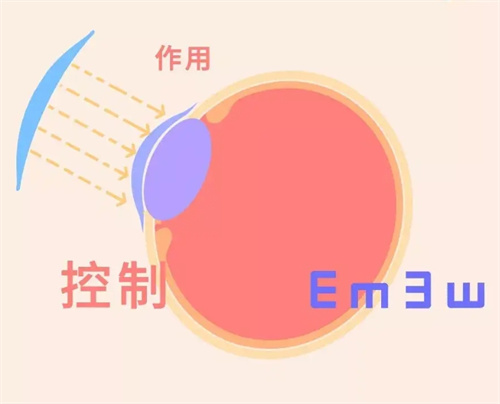

多焦点或散光矫正型人工晶体虽能改善视觉质量,但可能引发眩光、光晕等光学干扰。

尤其在夜间驾驶时,患者可能因灯光周围出现光晕而难以判断路况。一位ICL晶体植入患者反映,术后夜间看车灯时出现明显光晕,需避免夜间出行。

对比敏感度下降:视觉细节的“模糊滤镜”

人工晶体无法完全模拟自然晶状体的调节功能,患者术后可能感觉视觉对比度降低,尤其在暗光环境下难以分辨物体细节。

手术决策需综合考量眼部条件、全身健康状况及个人需求。对于高度近视患者,若角膜厚度不足无法接受激光手术,ICL晶体植入仍是优选;对于白内障患者,人工晶体置换是改善视力的仅有途径。